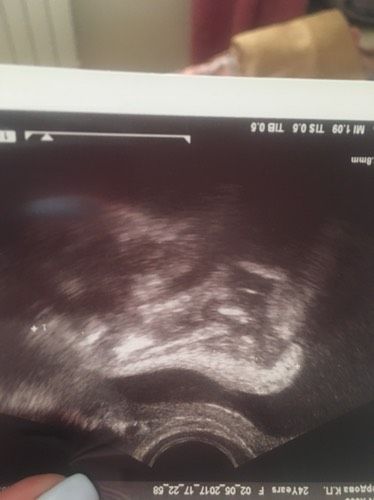

Сходила сегодня на узи, шейка вдруг стала больше 40,2 мм, сказали что неправильно измерили раньше ??♀️ как так?! Ну я рада таким показателям ? Один малыш весит около 1500г., второй 1300г. пуповина вокруг шеи и сидим на попе, а ноги около головы?, сказали если не перевернётся, то кесарево меня ждет. Все у нас хорошо ттт! Ходить уже тяжело, передвигаюсь, как ?, и потягивает низ живота)))) Фото лапки моего гномика в ленту.Перевернётся ещё малыш? Всем хорошего настроения?